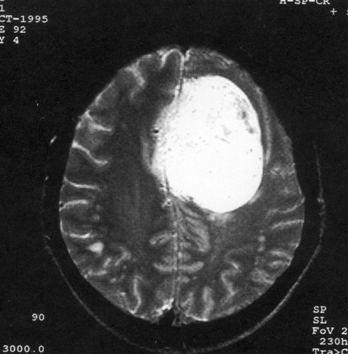

问题 病历摘要:??患者,男,40岁。发作性左下肢抽搐1年余,每次发作3~5分,每周发作1~2次。每次发作后感左下肢乏力,约半日后可自行恢复。既往身体健康。体检:神清,头顶部偏右有局限性骨性隆起(1.5×1.5cm),左鼻唇沟稍浅,伸舌居中。感觉、运动无明显异常。左浅反射减退,左下肢腱反射稍亢进,左Babinski征(-)。 术中下列哪些处理是错误的?提示:脑血管造影示上矢状窦中段闭塞,肿瘤有右脑膜中动脉和大脑前动脉分支供血。

选项 A.切皮前半小时给予抗生素 B.右顶开颅,切口至中线 C.电灼上矢状窦表面出血 D.对横跨在肿瘤表面的中央静脉电凝后切断 E.沿肿瘤和脑组织分界面以食指分离 F.连同肿瘤一起切除相连的矢状窦 G.切除受侵犯的硬膜,以人工脑膜修补 H.去除受侵犯的颅骨,以人工颅骨修补 I.术中静滴德巴金

答案 DE